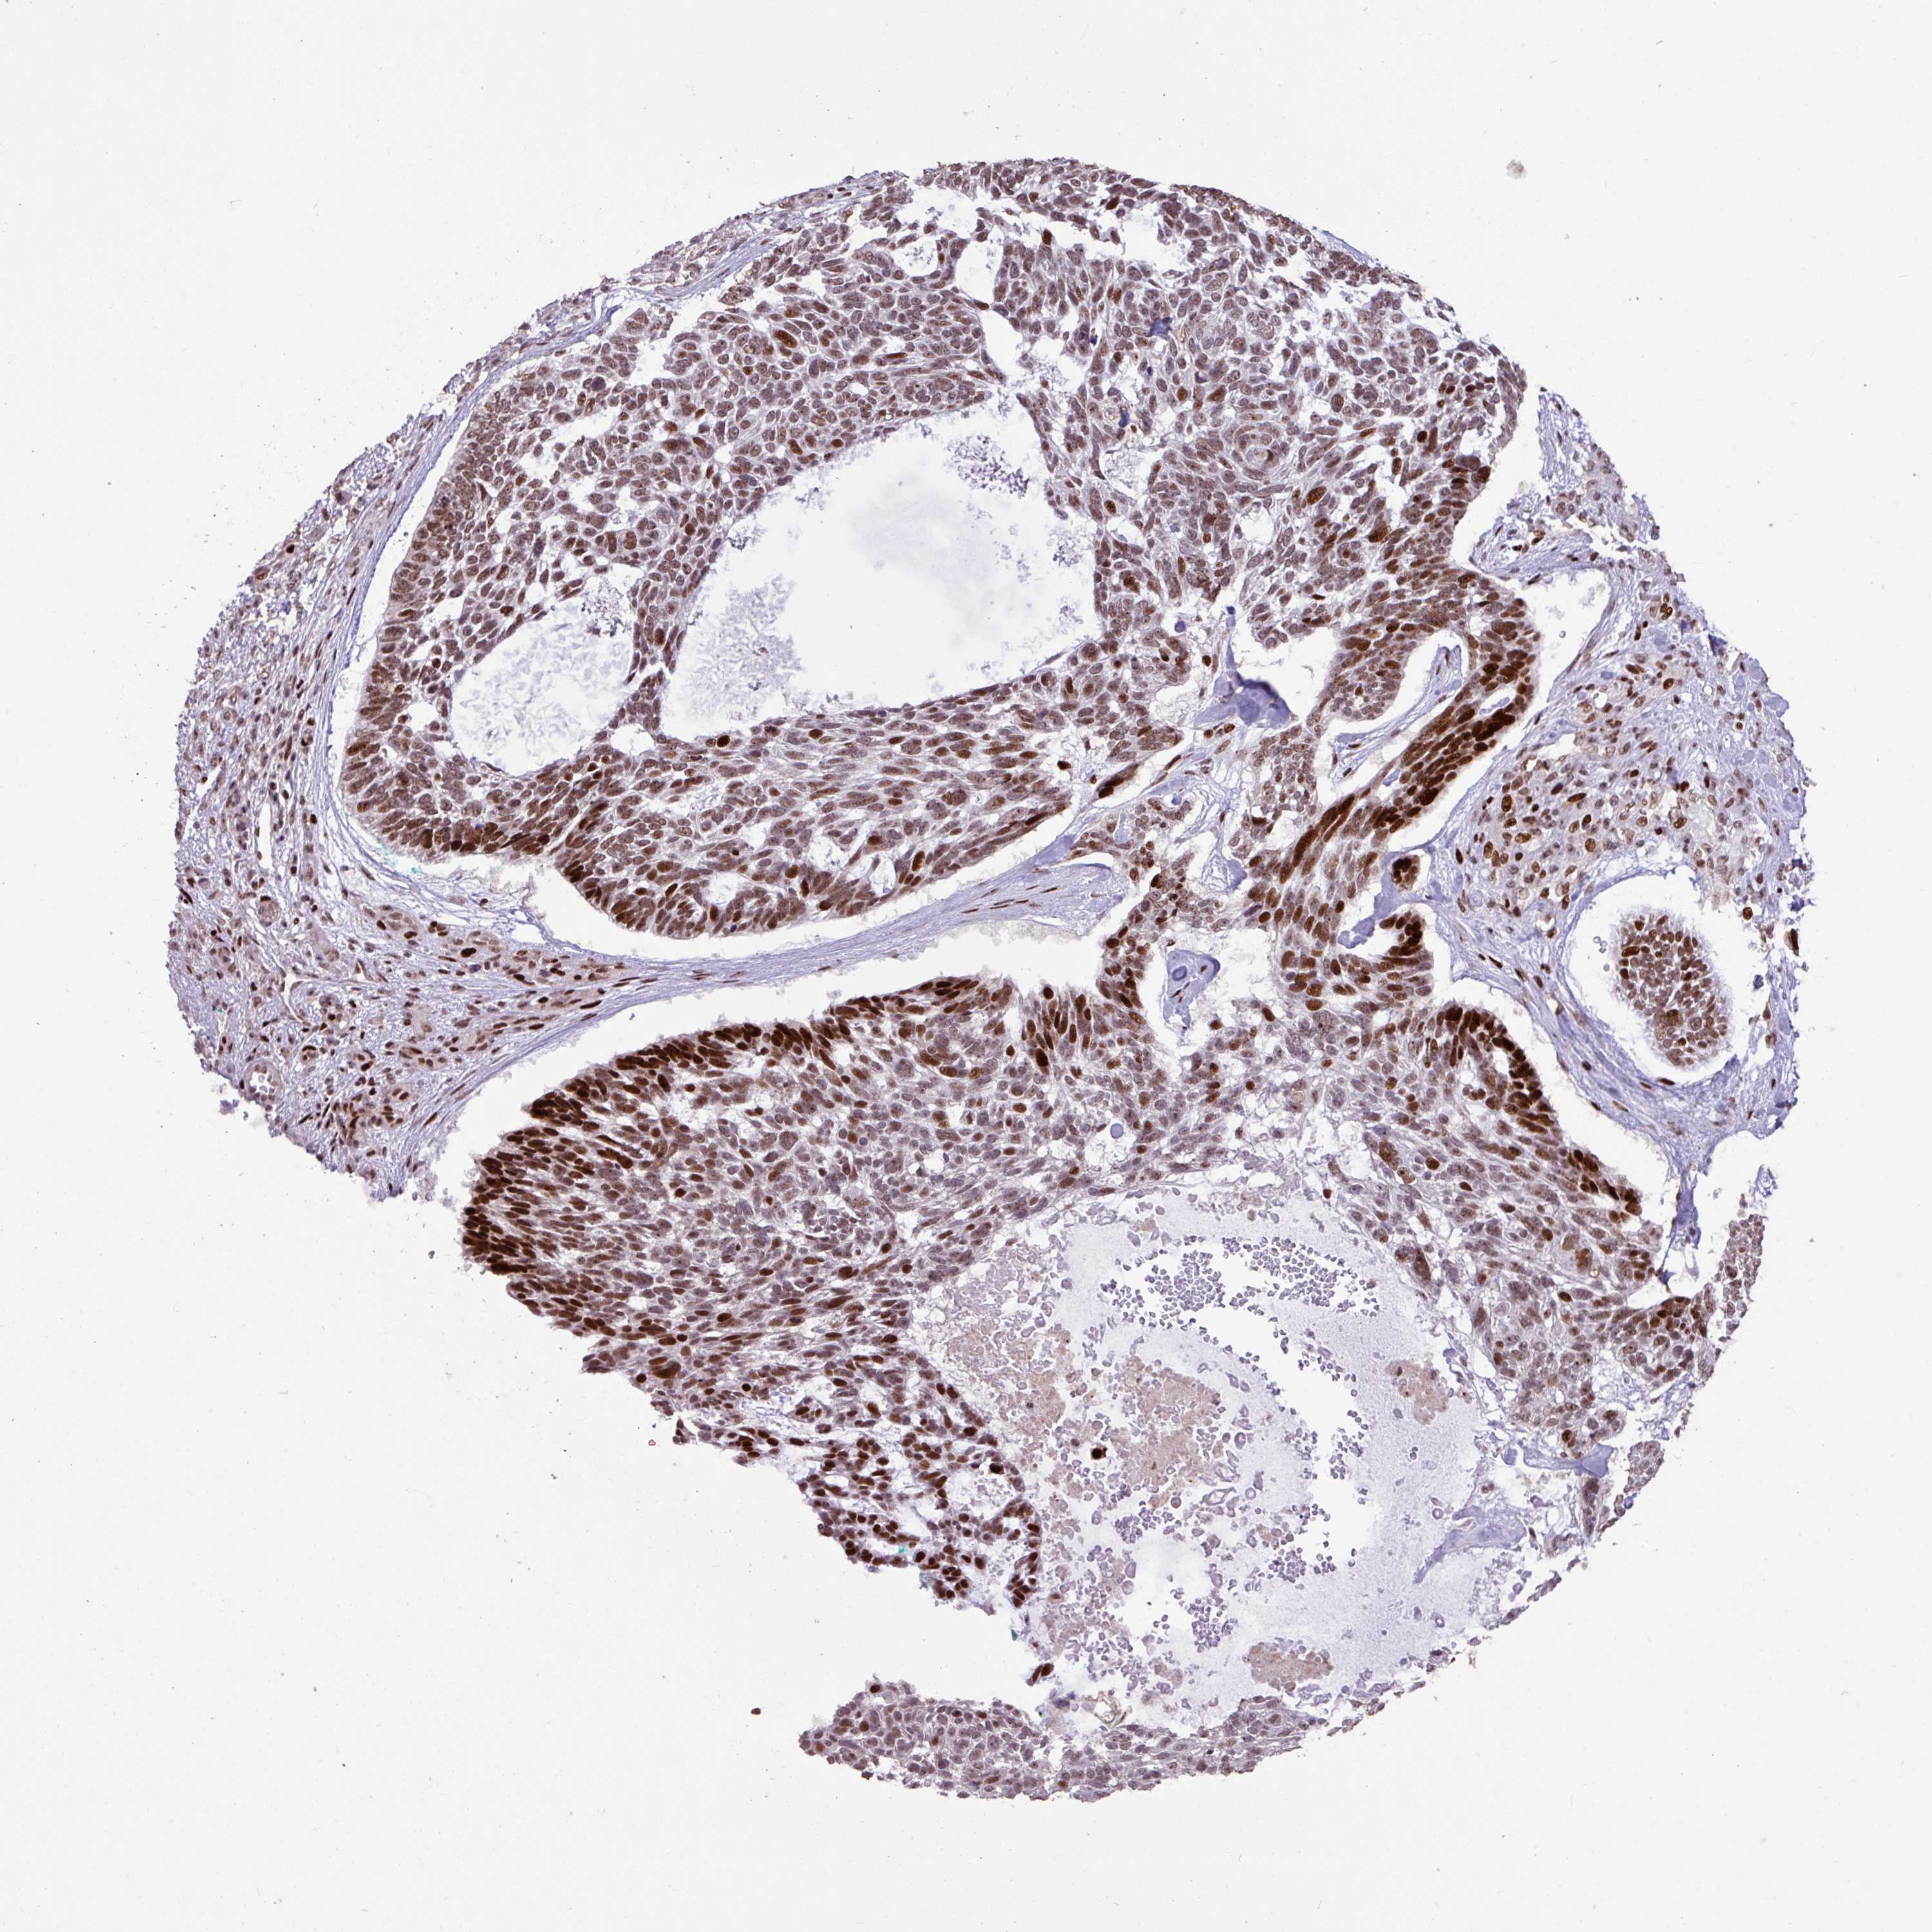

Basal cell and squamous cell cancer

SKIN CANCER - Protein expressioni

A mouse-over function shows sample information and annotation data. Click on an image to view it in a full screen mode. Samples can be filtered based on level of antibody staining by selecting one or several of the following categories: high, medium, low and not detected. The assay and annotation is described here.

Antibody HPA053153

Squamous cell carcinoma, NOS